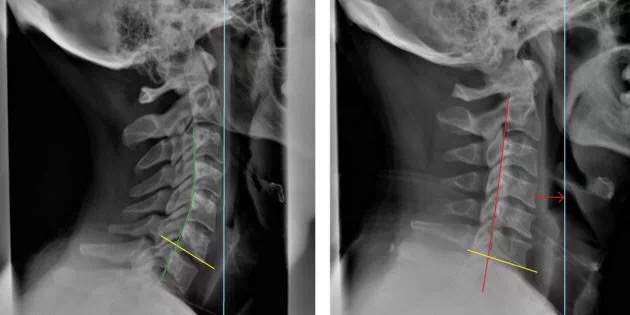

首先摆正耳垂,让两个耳垂水平(如红色的线),观察双肩的高度差,如果出现了双肩高度不一致的情况就要注意了,这就是我们常说的高低肩。那么高低肩人群应该拉伸哪一侧肌肉呢?现在从图中可以很清楚的看出,肩膀低的一侧肌肉被拉长,虽然平时你会觉得这一侧肌肉比较紧张,但是真的不能拉伸啊!反而要拉伸肩膀高的一侧,否则高低肩的情况会越来越严重!